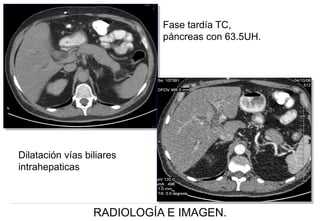

Imagen coronal y axial TC , donde se observa aumento del tamaño de la

Imagen axial TC fase arterial,

aumento difuso del tamaño del

con reforzamiento homogéneo

leve-moderado (77.1 UH )

y dilatación del colédoco (1.7 cms).

Imagen axial TC , en fase venosa

donde persiste retardo en la

perfusión del páncreas

(79.5UH), SIN evidencia de

lesión focal en la

glándula pancreática

Fase tardía TC,

páncreas con 63.5UH.

Dilatación vías biliares

intrahepaticas

IMPRESIÓN TOMOGRÁFICA:

Acorde con la literatura, con la

aumentada de tamaño de

forma difusa, en forma de

¨salchicha¨, de predominio

hacia la cabeza, con

atenuación homogénea y

reforzamiento moderado son

hallazgos de:

PANCREATITIS

AUTOINMUNE

Masculino de 64 años de edad con SxDAA CSD y sindrome icterico